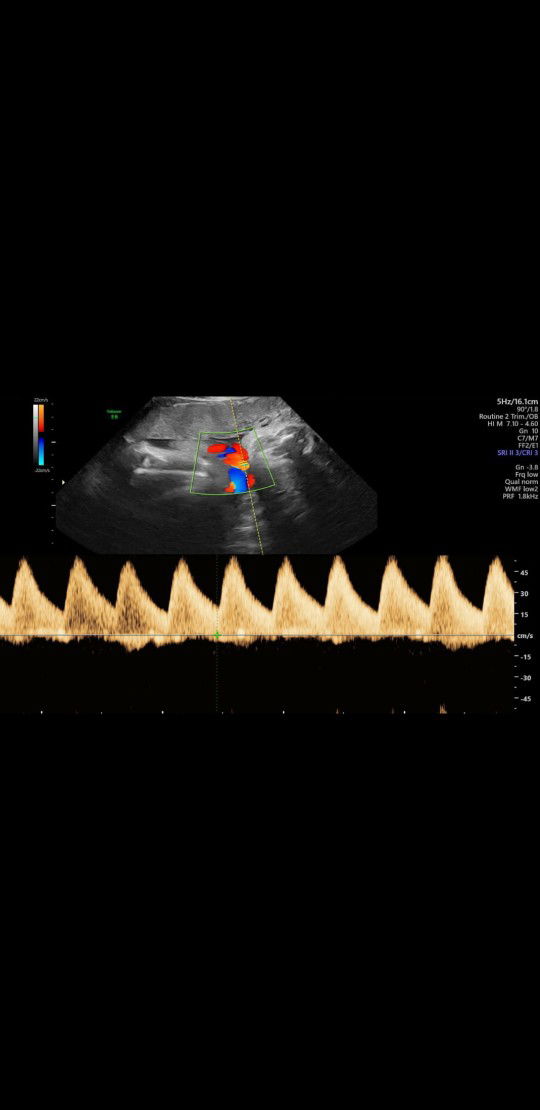

Halo bund.. Kemarin saya cek di dokter kandungan.. Usg ada liatin bagian tali pusar.. Dokternya bilang bagus.. Tapi ga ngejelasin apa apa.. Di tanya itu artinya merah biru apa juga cuma bilang bagus doang.. ??.. Saya jadi bingung.. Bun disini ad yang tau gak ya? Ini artinya wrn merah dan biru apa ya? Ada yang bisa bantu jawab bun?

Itu pembuluh darah yg merah biru